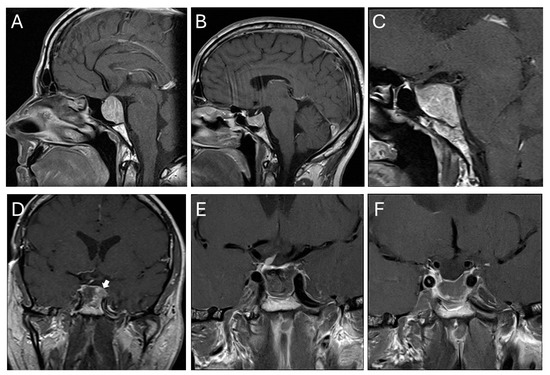

A 48-year-old male patient was diagnosed with a pituitary macroadenoma after a cranial MRI was performed due to a pituitary insufficiency (Figure 5A, patient number 13 in Table 1 and Table 3). The tumor expanded within the clival regions I and II and demonstrated a primary growth within the sella and clivus with a modified Knosp grade 2 lesion. Endocrinological work-up showed no evidence of hormone overproduction and total pituitary insufficiency. Due to the close contact to the optic chiasm (without visual deficits) and pituitary insufficiency, microscopic trans-sphenoidal resection was indicated and performed without complications. Histopathology revealed a null cell adenoma. The patient recovered without neurological deficit. The pituitary insufficiency however remained, and the patient received hydrocortisone, thyroxine and testosterone. Within the next three years, the patient showed an early recurrence (Figure 5B), however, without relevant suprasellar growth. Over the following 17 years, the tumor showed slow but steady growth (Figure 5C), now exclusively from the sella downwards into the clival regions I, II and III. Due to the constant growth and now significant size, a second surgery was performed via an endoscopic trans-sphenoidal approach. Intraoperatively, tumor delineation within the infiltrated cancellous bone proved difficult, particularly in the clival region III and towards the right cavernous sinus (Figure 5D). Intraoperative MRI helped to delineate residual tumor to be resected in the same surgical procedure (Figure 5E,F). Histopathology now revealed a silent gonadotrope adenoma. In both instances, the bony sella was diffusely eroded by the tumor, which invaded the cancellous clivus wherever it was in contact with the tumor and spread within it. Conversely, the tumor never showed any tendency to grow into the posterior fossa.

Figure 5. Illustrative case. (A) Preoperative imaging at the age of 48. The tumor predominantly grows within the sella and inferior to it with a minor suprasellar extension touching the optic chiasm. The tumor diffusely erodes the sellar bone, grows within regions I and II and respects the posterior fossa. (B) Early recurrence after three years. (C) Seventeen years after the first operation, the tumor demonstrated growth within all three clival regions. (D) Intraoperative MRI revealing residual tumor at the posterior part of the sella in contact with the left cavernous sinus. (E) Postoperative MRI after additional resection in the same surgical procedure. (F) MRI three months later. The white arrow in (D) shows tumor remnant on intraoperative MRI which was resected afterwards.